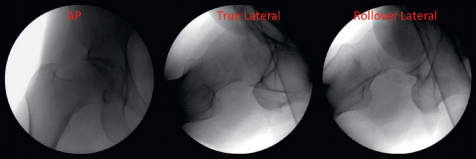

术前透视成像序列显示:患者为稳定性轻度外翻嵌插型股骨颈骨折,伴轻微股骨颈下段粉碎性骨折,矢状面未见台阶征或成角畸形(图8)。

什么是c型臂术中透视骨科精读 | 股骨近端骨折的转子区域与矢状面力线术中透视技巧_https://www.jmylbn.com_新闻资讯_第8张8

术后影像显示空心螺钉固定位置安全,通过宽间距倒置固定模式对骨折端实现有效加压(图9)。

什么是c型臂术中透视骨科精读 | 股骨近端骨折的转子区域与矢状面力线术中透视技巧_https://www.jmylbn.com_新闻资讯_第9张

图9